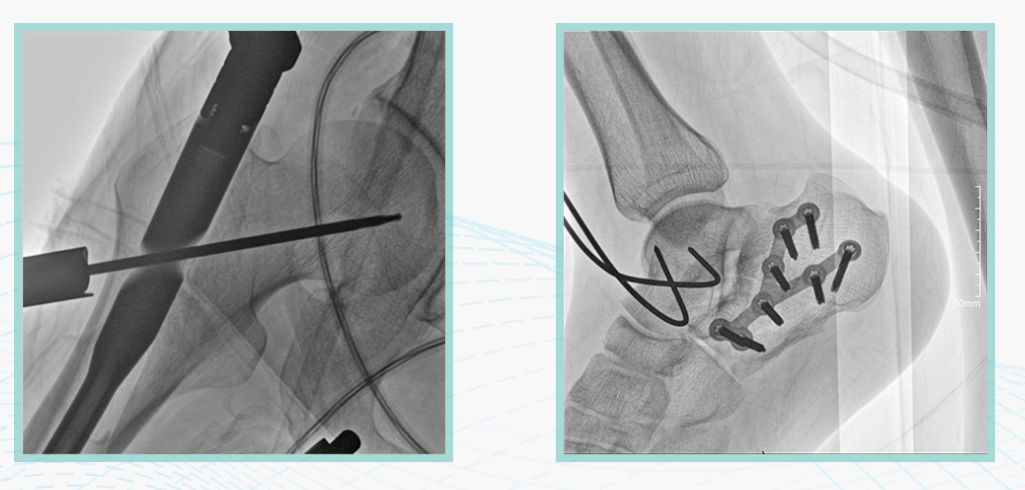

ty8天游平台登录科技悦画移动C臂X线摄影系统,采用了业内技术最尖端的CMOS探测器。基于性能优异的针状CSI闪烁体涂层和高灵敏度的CMOS感光芯片,悦画可以实现在超低X线剂量条件下实现高清晰影像成像,相较于一般的影增移动C臂和平板C臂,动态范围更高,影像的层次感和对比度更好。

在产品的性能参数设计上,悦画的像素可达到200万,空间分辨率可达到3.2线对,采用16bit的影像灰度,悦画在影像后处理上,通过SPI金字塔图像算法,支持摄影、脉冲透视影像、连续透视等多种模式下的影像采集,动态透视影像视频支持保存与回放。双大屏的设计,透视影像支持三档放大,保证临床影像读取的便利。

悦画在影像的伪影处理上,也积累多项图像处理专利技术。通过对植入物的精准识别,悦画能够精准祛除植入物伪影与运动伪影,保证高质量的影像输出,无论是影像的对比度、分辨率(清晰度)相较于市面上的移动C臂产品都更胜一筹。